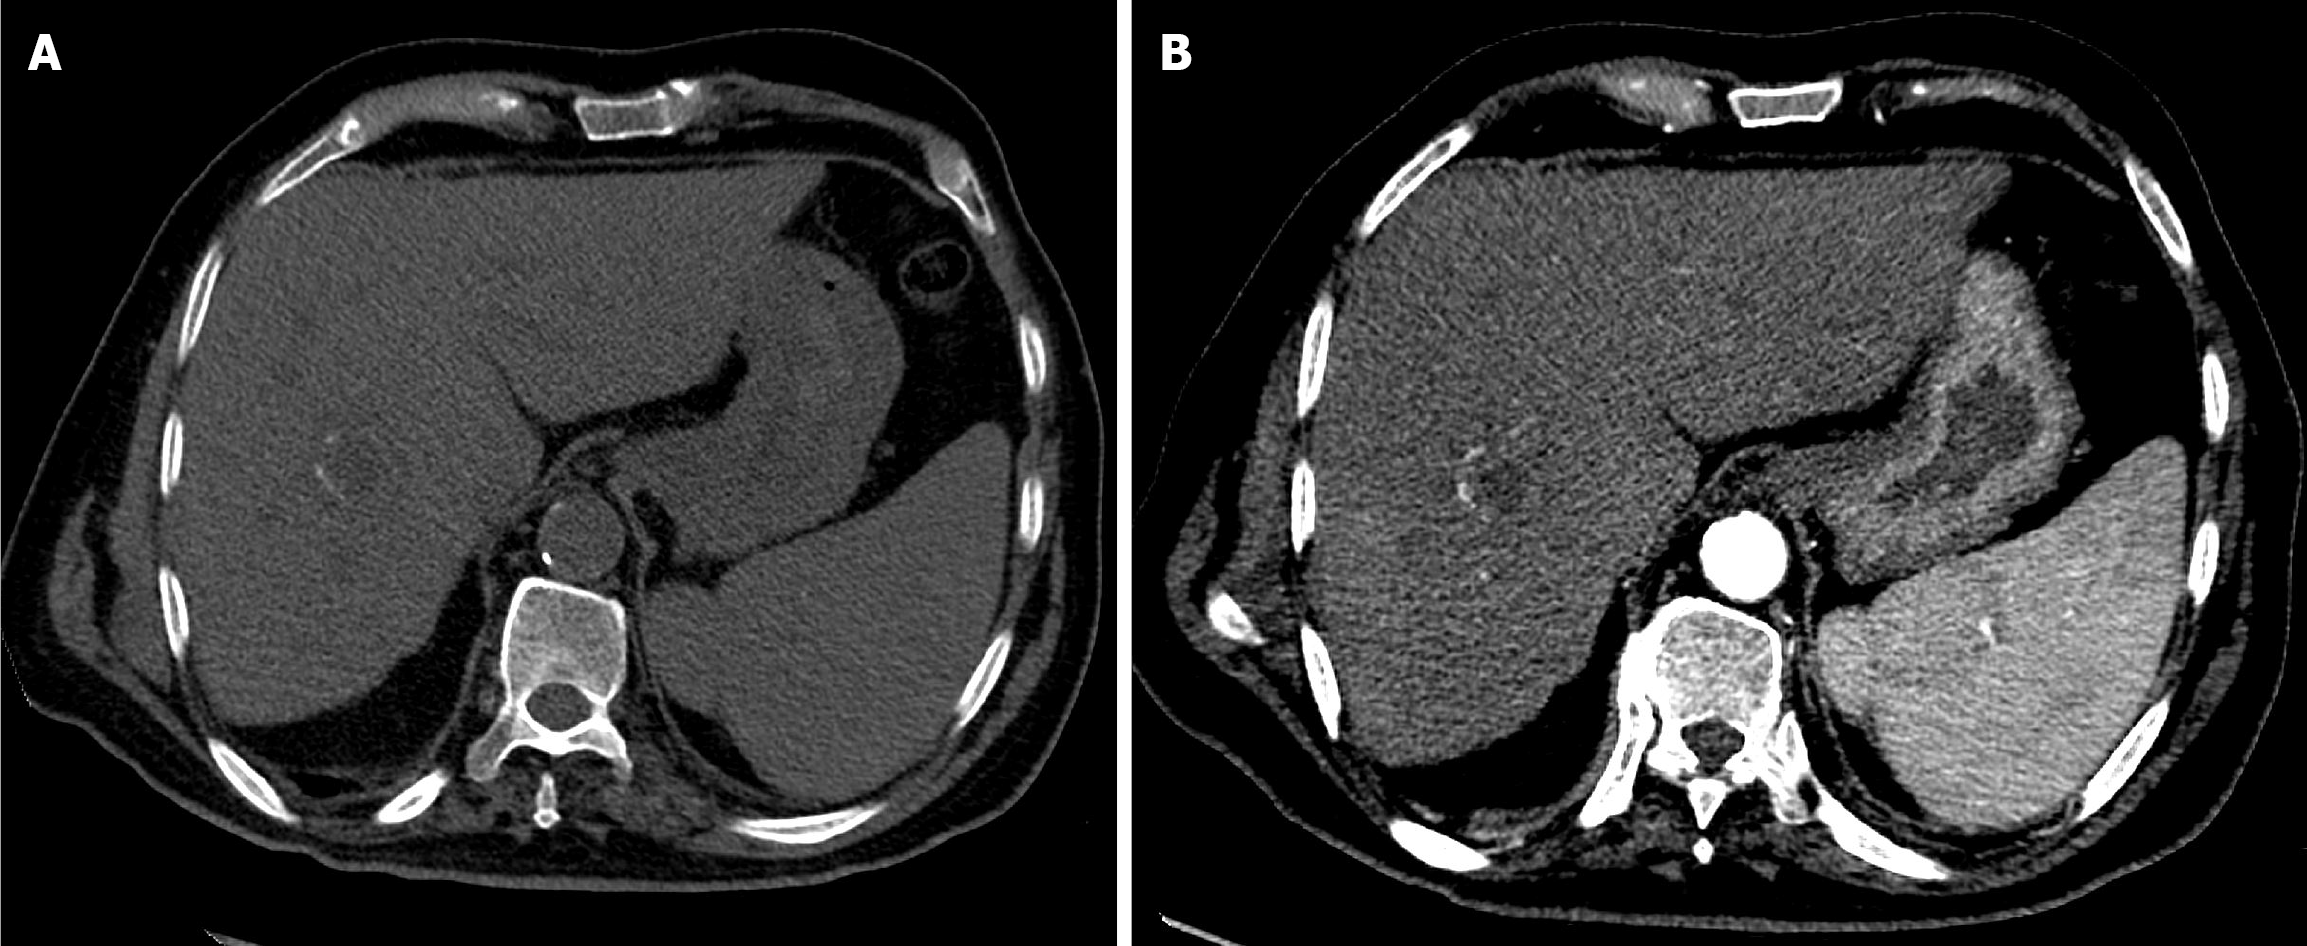

Figure 6 Four-week follow-up computed tomography of the abdomen after the second drug-eluting bead transarterial chemoembolization in Case 1.

A: Arterial phase computed tomography (CT) showed a non-enhancing mass, consistent with complete response; B: Portal venous phase CT demonstrated normal hepatic parenchymal enhancement with a necrotic treated mass.